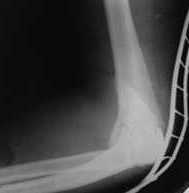

Опять постепенно в течении 8 нед после повторной операции постепенно движения ограничились

до 80 - 110, на снимке оссификат. Снимки во вложении, буду рад Вашим советам. Спасибо!